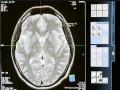

Boston [US], June 10 : Researchers have found brain network connections linked to anosognosia. This study was published in ... ...